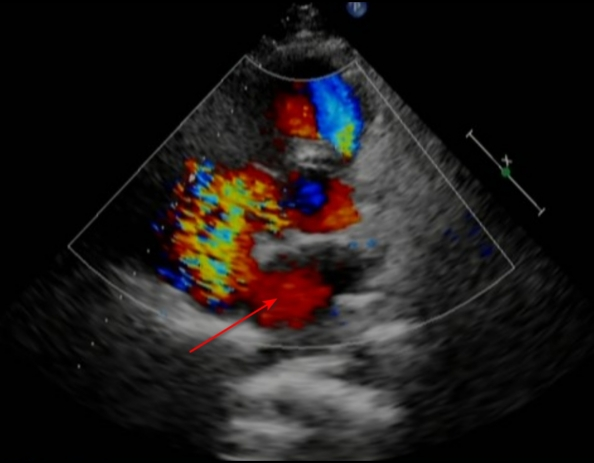

术后的心脏超声显示,主动脉和肺动脉的内径恢复正常,主动脉无冠窦能看到补片的强回声,动脉水平的分流也消失了。患者恢复状况良好,现已康复出院。